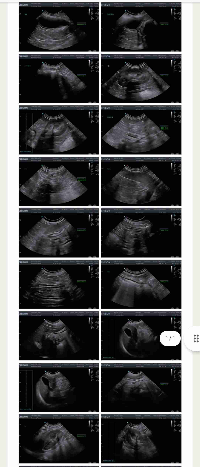

Ajude a Fedora a lutar pela vidaEssa é a Fedora, uma cachorrinha doce e companheira que está enfrentando uma batalha difícil. Recentemente, ela foi diagnosticada com uma inflamação uterina grave (piometra), que colocou sua vida em risco. O diagnóstico foi confirmado por um veterinário da clínica DiPaulla em 21/05/2025 e exige tratamento imediato para que ela tenha chances de se recuperar.Fedora precisa urgentemente de cuidados médicos, exames e medicamentos. O custo total estimado do tratamento é de R$ 2.200,00, valor que está além das possibilidades da cuidadora neste momento.Cada contribuição, por menor que seja, pode fazer toda a diferença para salvar a vida da Fedora.Se você puder ajudar, clique no link da vaquinha e contribua. E mesmo que não possa doar agora, compartilhar esta campanha já é uma grande ajuda.Vamos juntos dar à Fedora a chance que ela merece.